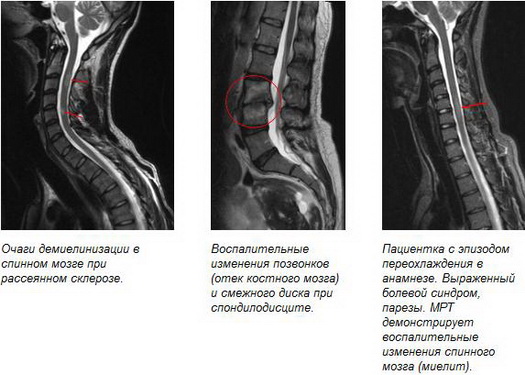

МРТ позвоночника на сегодняшний день основной метод выбора в диагностике грыж межпозвонковых дисков, являющихся наиболее частой причиной болей в позвоночнике (до 80%), а также других дегенеративно-дистрофических заболеваний позвоночника, воспалительных и опухолевых изменений позвонков, мягких тканей и структур спинного мозга.

На сегодняшний день МРТ – оптимальный метод скрининговой и дифференциальной диагностики патологических изменений спинного мозга, а также единственный метод диагностики его демиелинизирующих заболеваний.

• демиелинизирующие процессы (рассеянный склероз, острый рассеянный энцефаломиелит). В данном случае МРТ – единственный метод инструментальной диагностики демиелинизирующих заболеваний;

• демиелинизирующие процессы (рассеянный склероз, острый рассеянный энцефаломиелит). МРТ – единственный метод инструментальной диагностики демиелинизирующих заболеваний;